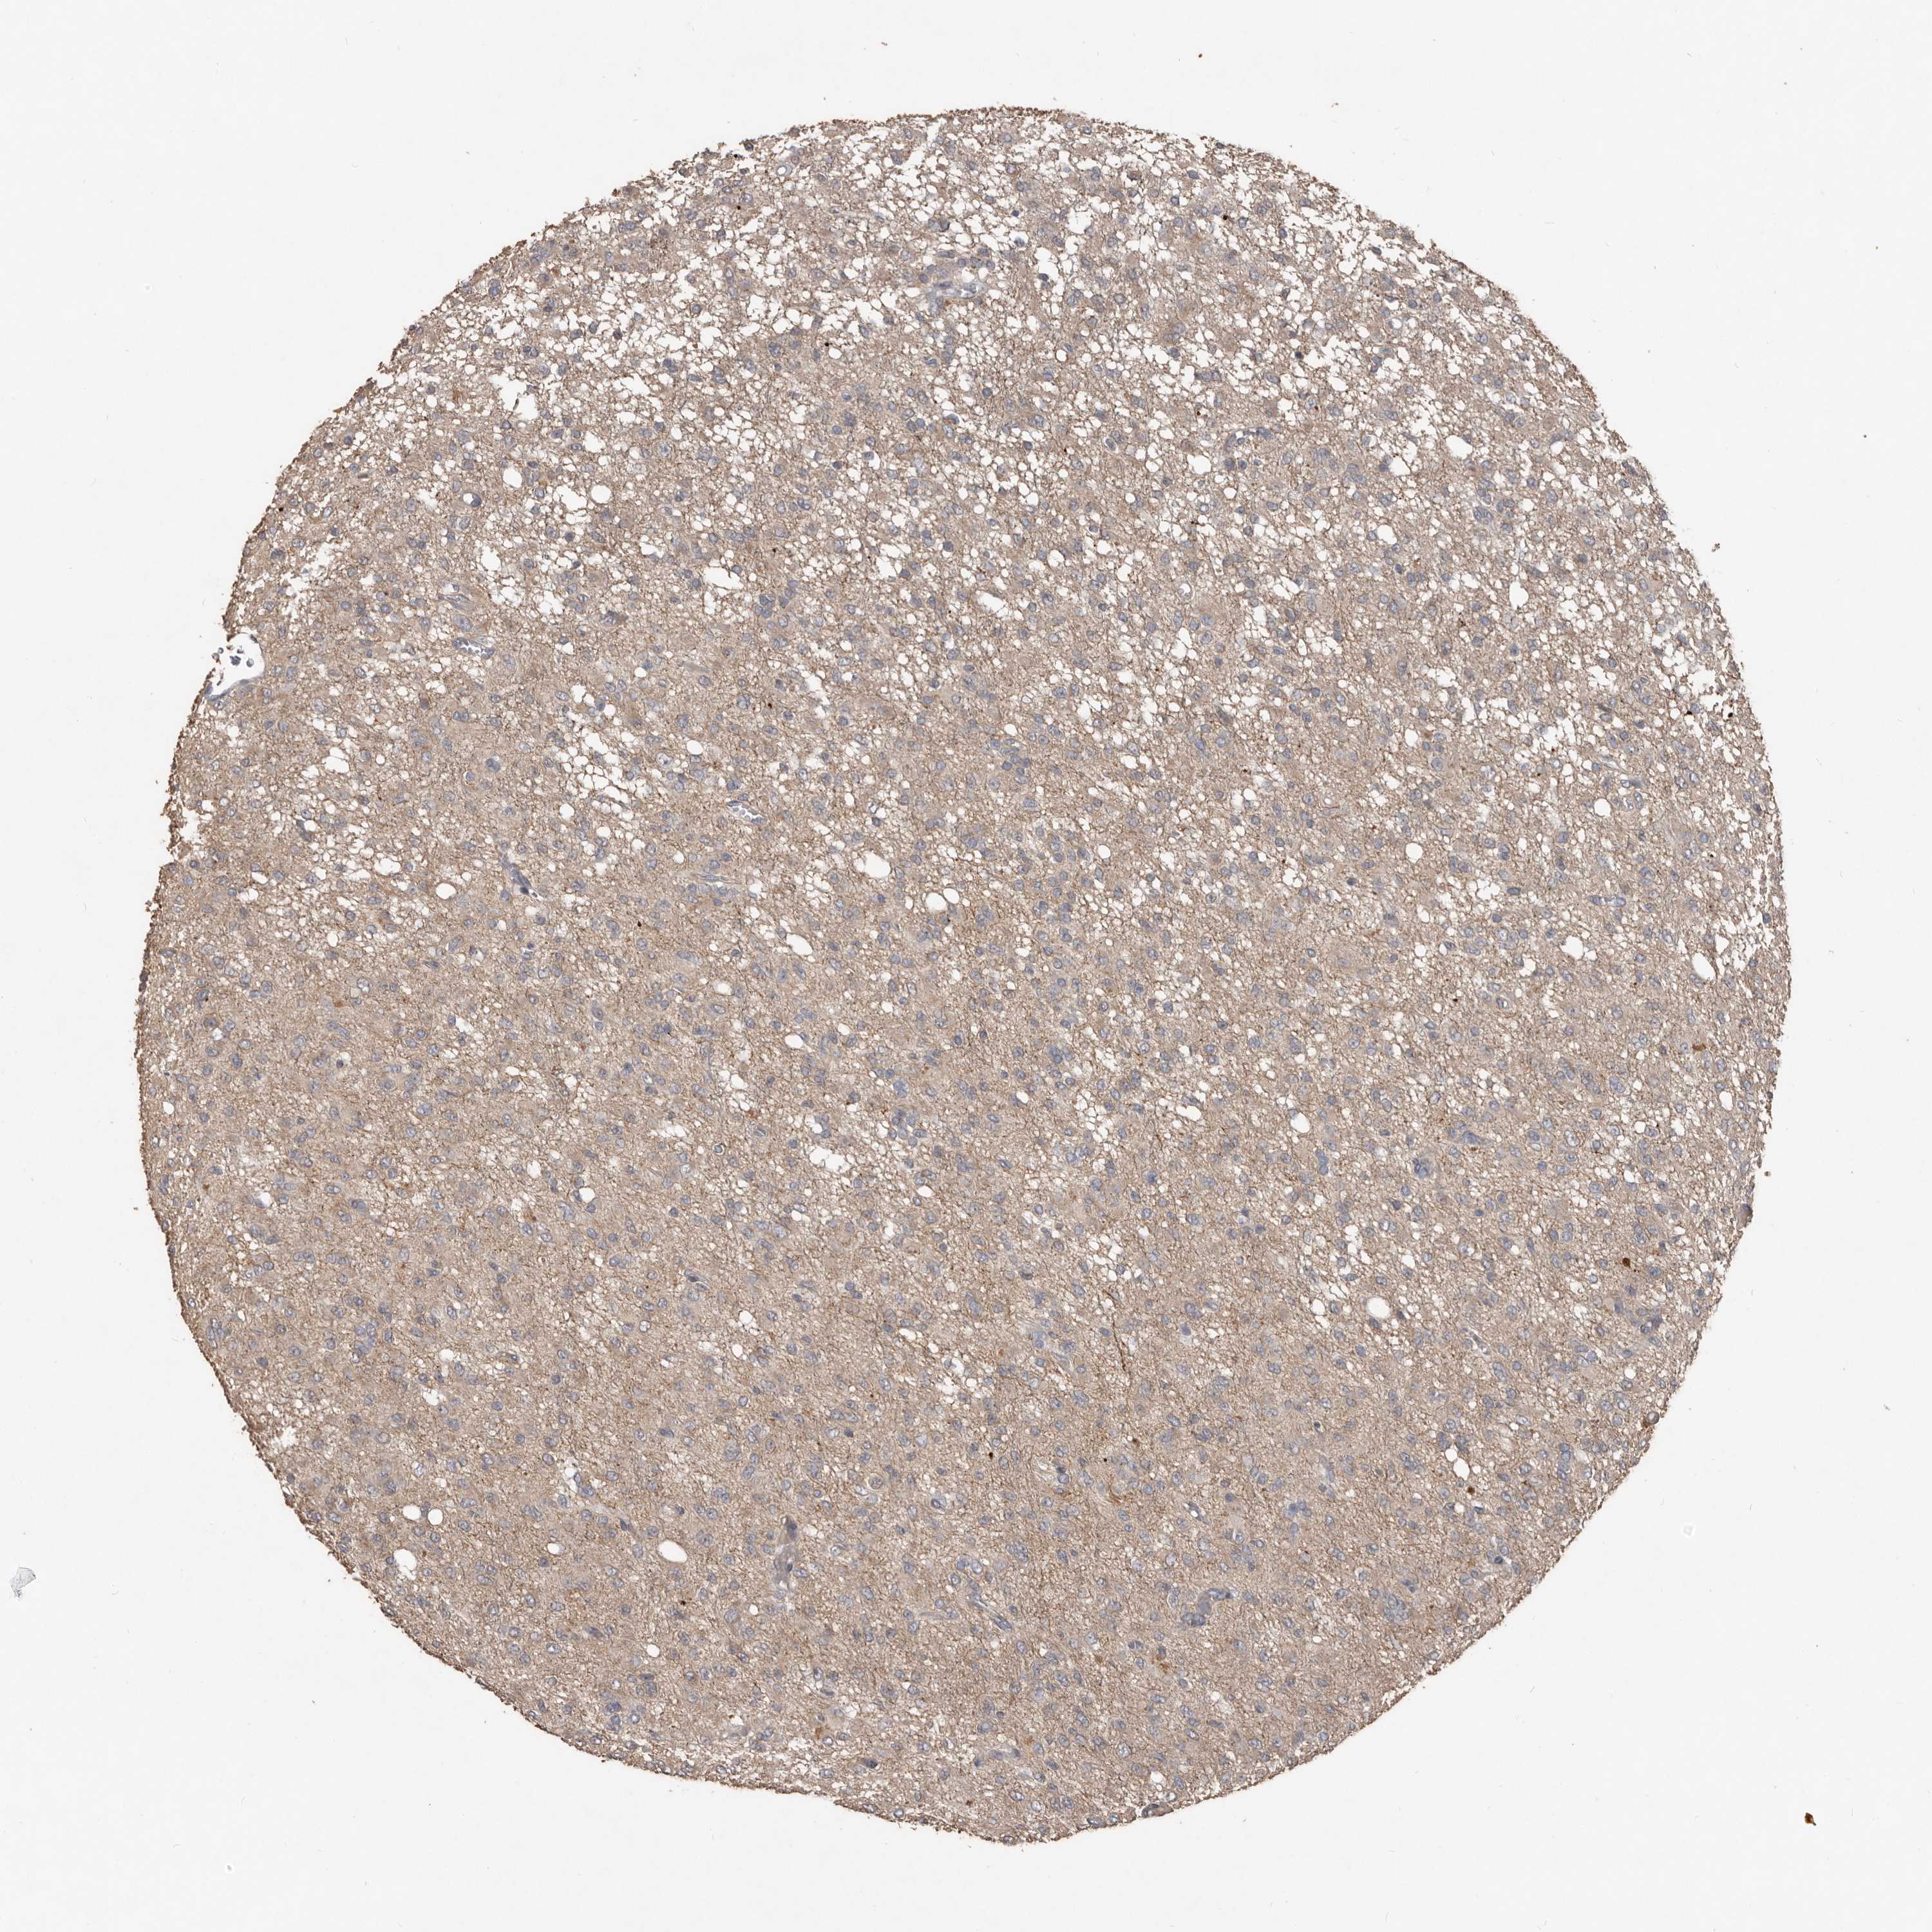

GLIOMA - Protein expressioni

A mouse-over function shows sample information and annotation data. Click on an image to view it in a full screen mode. Samples can be filtered based on level of antibody staining by selecting one or several of the following categories: high, medium, low and not detected. The assay and annotation is described here.

Note that samples used for immunohistochemistry by the Human Protein Atlas do not correspond to samples in the TCGA dataset.

Antibody stainingi

Antibody staining in the annotated cell types in the current human tissue is reported as not detected, low, medium, or high, based on conventional immunohistochemistry profiling in selected tissues. This score is based on the combination of the staining intensity and fraction of stained cells.

Each image is clickable and will lead to virtual microscopy that enables deeper exploration of all samples and also displays staining intensity scores, fraction scores and subcellular localization as well as patient and tissue information for each sample.

Antibody HPA010866

Staining

High

Medium

Low

Not detected

Intensity

Strong

Moderate

Weak

Negative

Quantity

>75%

75%-25%

<25%

None

Location

Nuclear

Cytoplasmic/membranous

Cytoplasmic/membranous,nuclear

Glioma, malignant, High grade

Glioma, malignant, Low grade

Glioblastoma, NOS